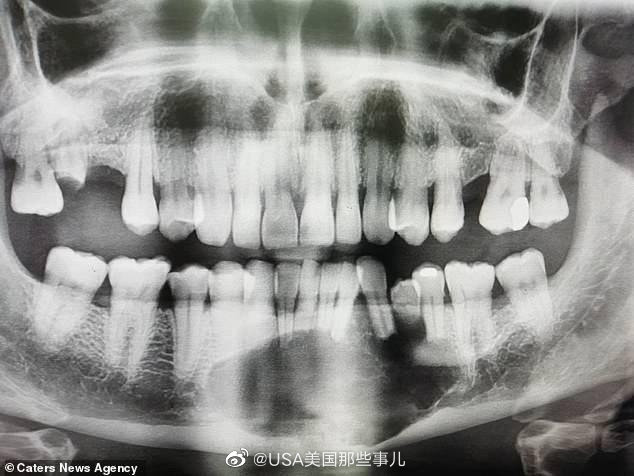

牙瘤x线图片

x线片示:右下第二乳磨牙阻生,合面见两个高度钙化物影像,右下第二双